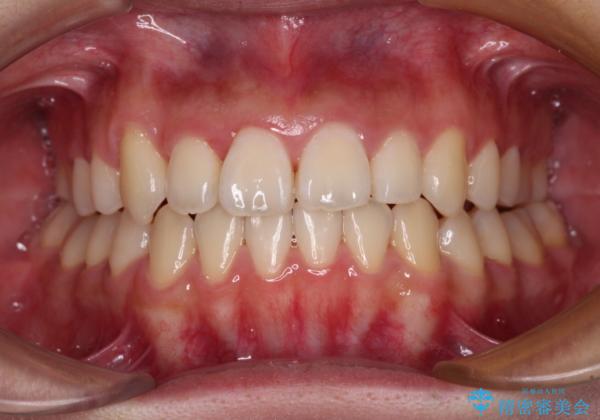

- 前歯の開咬と、上顎前歯の八重歯やデコボコを気にして来院された患者様です。

上顎歯列が狭窄していたため、急速拡大装置により上顎骨を側方に拡大し、その後ワイヤー装置にて矯正治療を行うこととしました。

上顎骨を拡大することで、八重歯やデコボコを歯列に収めることができ、下顎の歯が外に位置していた奥歯の咬み合わせも改善することができました。

スペースも短期間に獲得できるため、1年程度で治療を終えることができました。